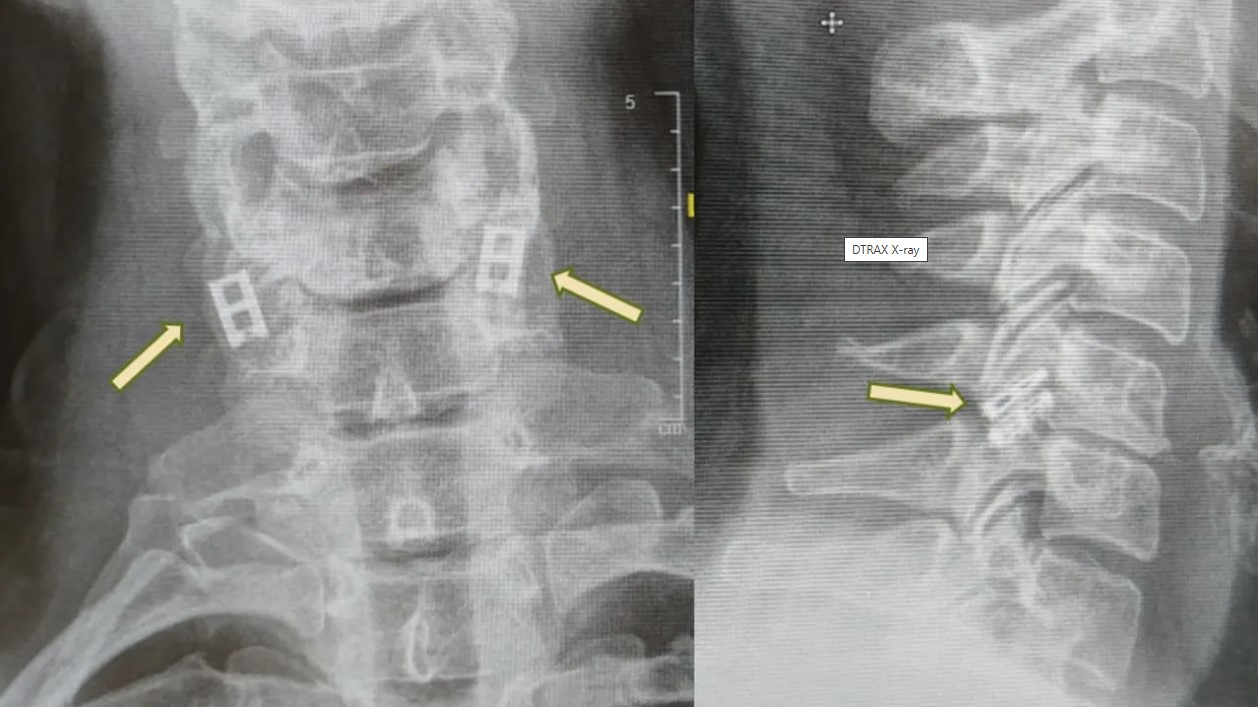

Προς το παρόν, οι τραυματισμοί του νωτιαίου μυελού δεν μπορούν να θεραπευτούν πλήρως, επομένως η θεραπεία επικεντρώνεται στη σταθεροποίηση του ασθενούς, την πρόληψη περαιτέρω προβλημάτων και τη μεγιστοποίηση της λειτουργικότητας. Η επείγουσα φροντίδα περιλαμβάνει συχνά την ακινητοποίηση της σπονδυλικής στήλης, τη μείωση της φλεγμονής και σε ορισμένες περιπτώσεις τη χειρουργική επέμβαση για αποκατάσταση καταγμάτων ή την ανακούφιση από πίεση.

Σε αντίθεση με άλλους ιστούς, οι νευρώνες του νωτιαίου μυελού δεν μπορούν να αναγεννηθούν φυσικά, και με την πάροδο του χρόνου, ο ουλώδης ιστός εμποδίζει τα εναπομείναντα σήματα. Η νέα διαδικασία στοχεύει στην αντικατάσταση του κατεστραμμένου τμήματος με εργαστηριακά καλλιεργημένο νωτιαίο μυελό που συγχωνεύεται με τον υγιή ιστό πάνω και κάτω από το σημείο του τραυματισμού.

Επίσης, συλλέγεται λιπώδης ιστός για τη δημιουργία μιας προσαρμοσμένης υδρογέλης (scaffold), στην οποία τα κύτταρα αυτά αναπτύσσονται σε δομή νωτιαίου μυελού. Αυτός ο τεχνητός ιστός εμφυτεύεται, αντικαθιστώντας τις ουλές και επανασυνδέοντας το νευρικό σύστημα.